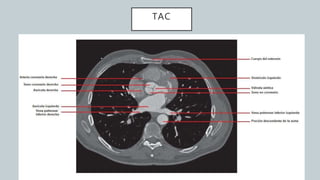

El documento detalla la anatomía del corazón y su ubicación en la caja torácica, incluyendo estructuras como las aurículas, ventrículos y arterias. También se abordan técnicas de diagnóstico por imagen, como radiografías y TAC, para visualizar la morfología cardíaca. La información está dirigida a estudiantes de medicina y profesionales interesados en la anatomía cardíaca.